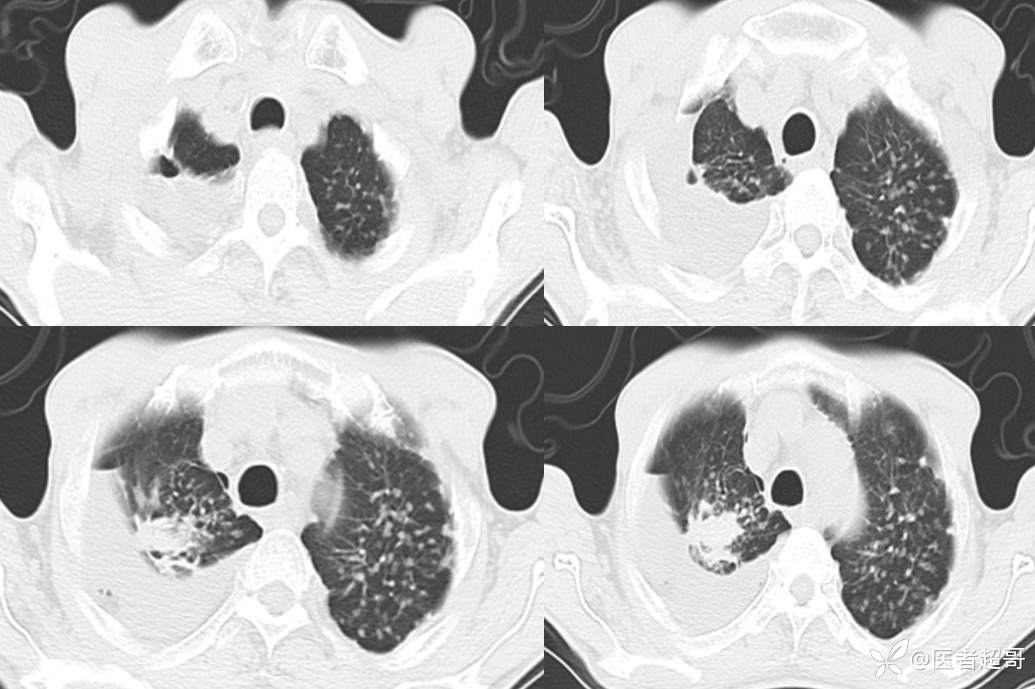

患者,男,72岁,农民,于2021年05月26日17时20分因"发作性精神行为异常10+天"入院。@丁香影像频道

肺炎支原体肺炎 (105)